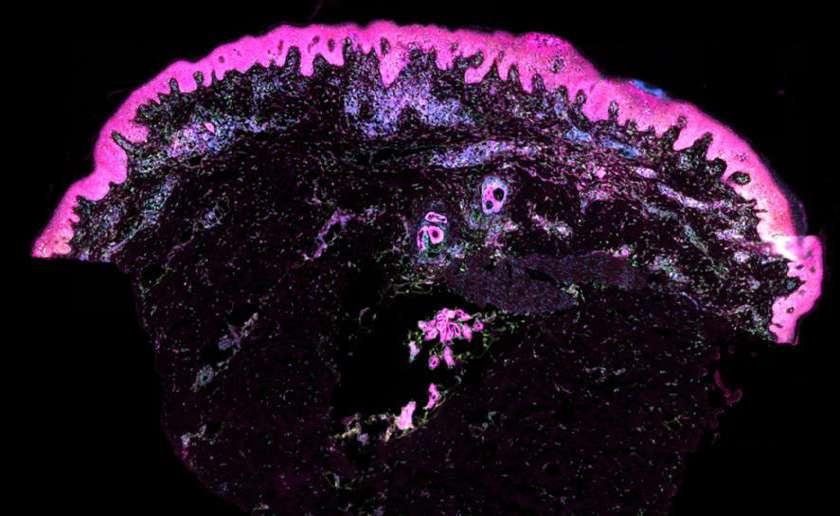

El estudio revela los cambios celulares que regulan el desarrollo de la piel ofreciendo esperanza en la medicina regenerativa.

Un equipo de investigadores del Instituto Wellcome Sanger y la Universidad de Newcastle ha desarrollado un atlas unicelular y espacial de la piel humana prenatal. Este avance ofrece una “receta molecular” para construir piel y mejorar los tratamientos clínicos, como los trasplantes para víctimas de quemaduras o personas con alopecia cicatricial. La in -

vestigación, publicada en la revista Nature, utiliza técnicas genómicas avanzadas para analizar cómo se forma la piel y sus folículos pilosos.

Desarrollo de la piel Gracias a la secuenciación unicelular, los científicos descompusieron muestras de tejido cutáneo prenatal para observar las células individuales en su con -

texto dentro del tejido. El estudio revela los cambios celulares que regulan el desarrollo de la piel, lo que podría ser clave para prevenir cicatrices tras cirugías o heridas. Además, el equipo creó un organoide, o “mini órgano”, de piel con la capacidad de hacer crecer el pelo. Añadieron macrófagos, células inmunitarias, al organoide, descubrien -

do que juegan un papel crucial en la formación de vasos sanguíneos. Este hallazgo puede tener implicaciones en la mejora de la cicatrización y el crecimiento de la piel en trasplantes. Estos avances podrían ayudar a víctimas de quemaduras o personas con alopecia cicatricial, una condición que destruye permanentemente los folículos pilosos. (EFE)

Elena Winheim, del Wellcome Sanger, resume que el atlas proporciona la primera ‘receta molecular’ para crear piel humana.

Nuevos hallazgos sobre la formación de la piel abren camino a trasplantes

Estos avances podrían ayudar a víctimas de quemaduras o personas con alopecia cicatricial, una condición que destruye permanentemente los folículos pilosos. 10